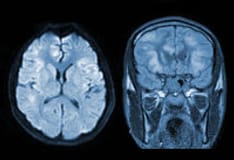

The image below lists drugs that impair water excretion.

Drugs that impair water excretion.